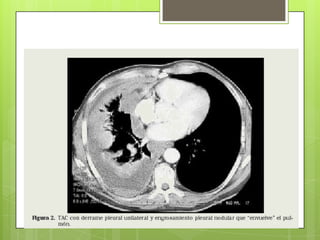

RADIOGRAFÍA Y ESPIROMETRÍA

 Imágenes lineales en campos inferiores y

engrosamiento de pleura parietal 

calcifican (>20 años)

COMPLICACIONES

 Carcinoma broncogénico: adenoCa, Ca

de células pequeñas o Ca epidermoide

 Mesotelioma maligno 5-8%

 Derrame pleural “benigno” (precoz)

 Insuficiencia respiratoria

 Cor pulmonale